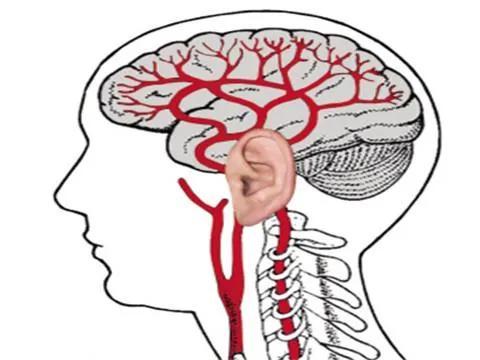

人到中老年,脑血管就会出现硬化,是中风的基础病变,但早期临床上没有明显症状,出现的头晕眼花,失眠多梦不适多数是脑供血不足的表现,与早期的脑血管硬化关系不大。

中老年人可以进行头部CT、颈部血管彩超,经颅多普勒,磁共振等设备的检查,可以评判颅内血管的状态。